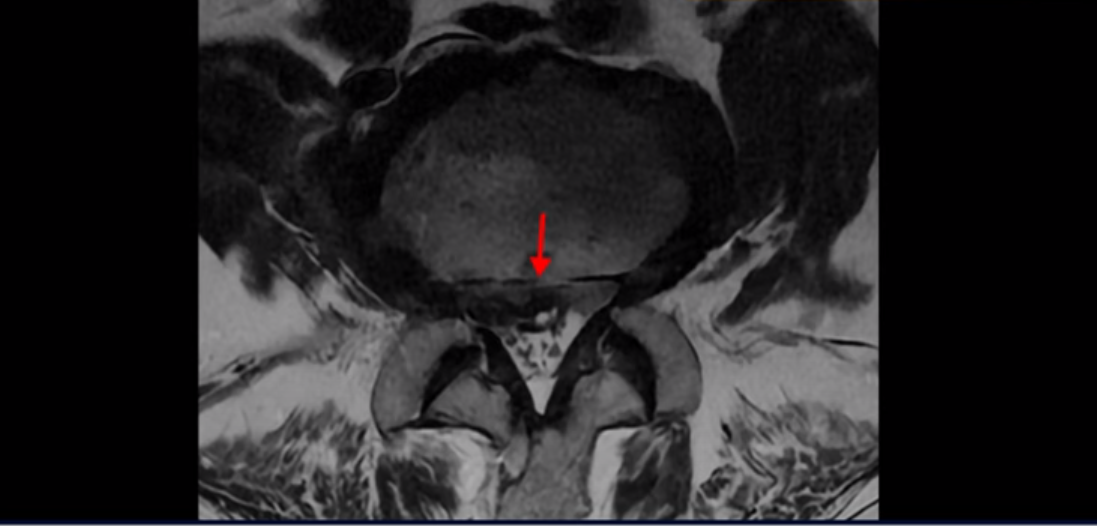

3번 4번에는 척추관협착과 디스크 탈출이 보이고

4번 5번에는 척추관협착과 심한 디스크 파열이 있습니다.

기립근의 지방화도 심합니다. 또 3번 4번 마디에서는 신경가지가 빠져나가는 추간공이 왼쪽, 오른쪽 모두 많이 좁아져 있습니다.

이런 이유로 이 환자분은 왼쪽 다리는 마비가 생겨 힘이 빠지고 오른쪽 다리에는 심한 방사통이 있어서 휠체어까지 타야 하는 상태가 되었습니다. 이렇게 심하니까 대학병원에서 여러 마디 나사를 박는 유합술을 권유 받으셨는데요.